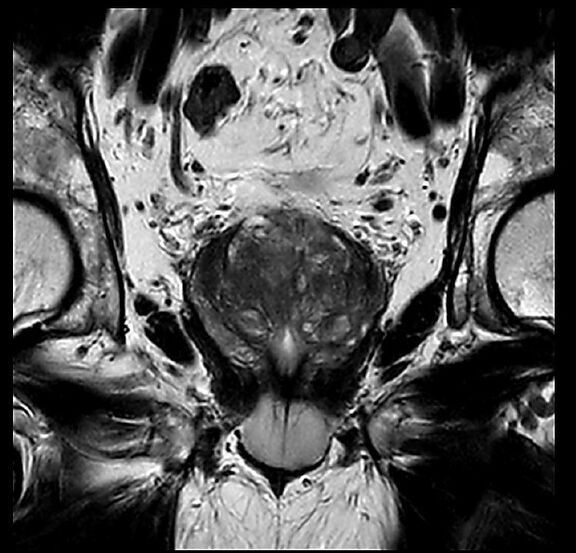

Beispiele von MRT-Prostata Aufnahmen

Die MRT wird meist zur Abklärung von Auffälligkeiten in der Prostata eingesetzt, die bei anderen Untersuchungen wie einer Tastuntersuchung, einer Blutuntersuchung oder einem PSA-Test festgestellt wurden. Dazu gehören zum Beispiel eine Vergrößerung der Prostata oder der Verdacht auf Prostatakrebs. Neben der Diagnose von Prostatakrebs können auch andere Erkrankungen wie Entzündungen oder gutartige Vergrößerungen der Prostata im MRT erkannt werden. Dies ermöglicht eine gezielte und schnelle Therapie.

Ein großer Vorteil der MRT im Vergleich zu anderen Verfahren ist die hohe Genauigkeit bei der Erkennung von Prostatakrebs im Vergleich zu anderen Verfahren. Die MRT kann die Gewebestrukturen der Prostata gezielt abbilden und so kleinste Veränderungen sichtbar machen. Zudem ist die Untersuchung schonender und kommt ohne den Einsatz von Röntgenstrahlung aus.